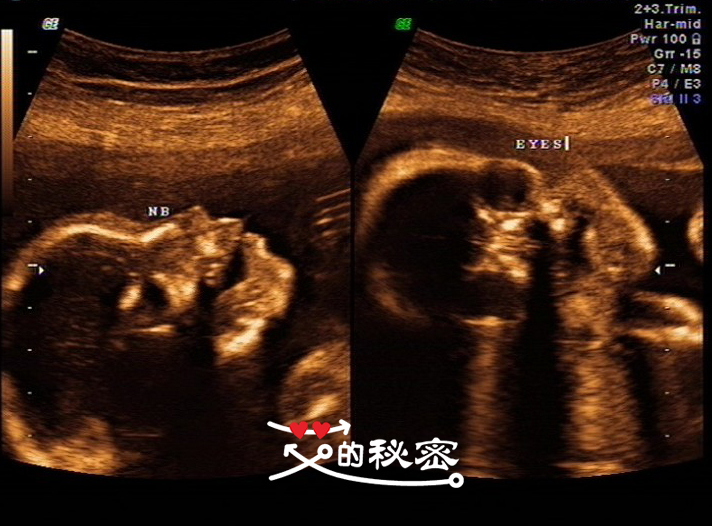

6、胎儿颜面部:双眼、鼻梁鼻孔可见,上唇回声未见明显连续性中断。双耳廓可见。英文的意思:NB鼻子,EYES眼睛。